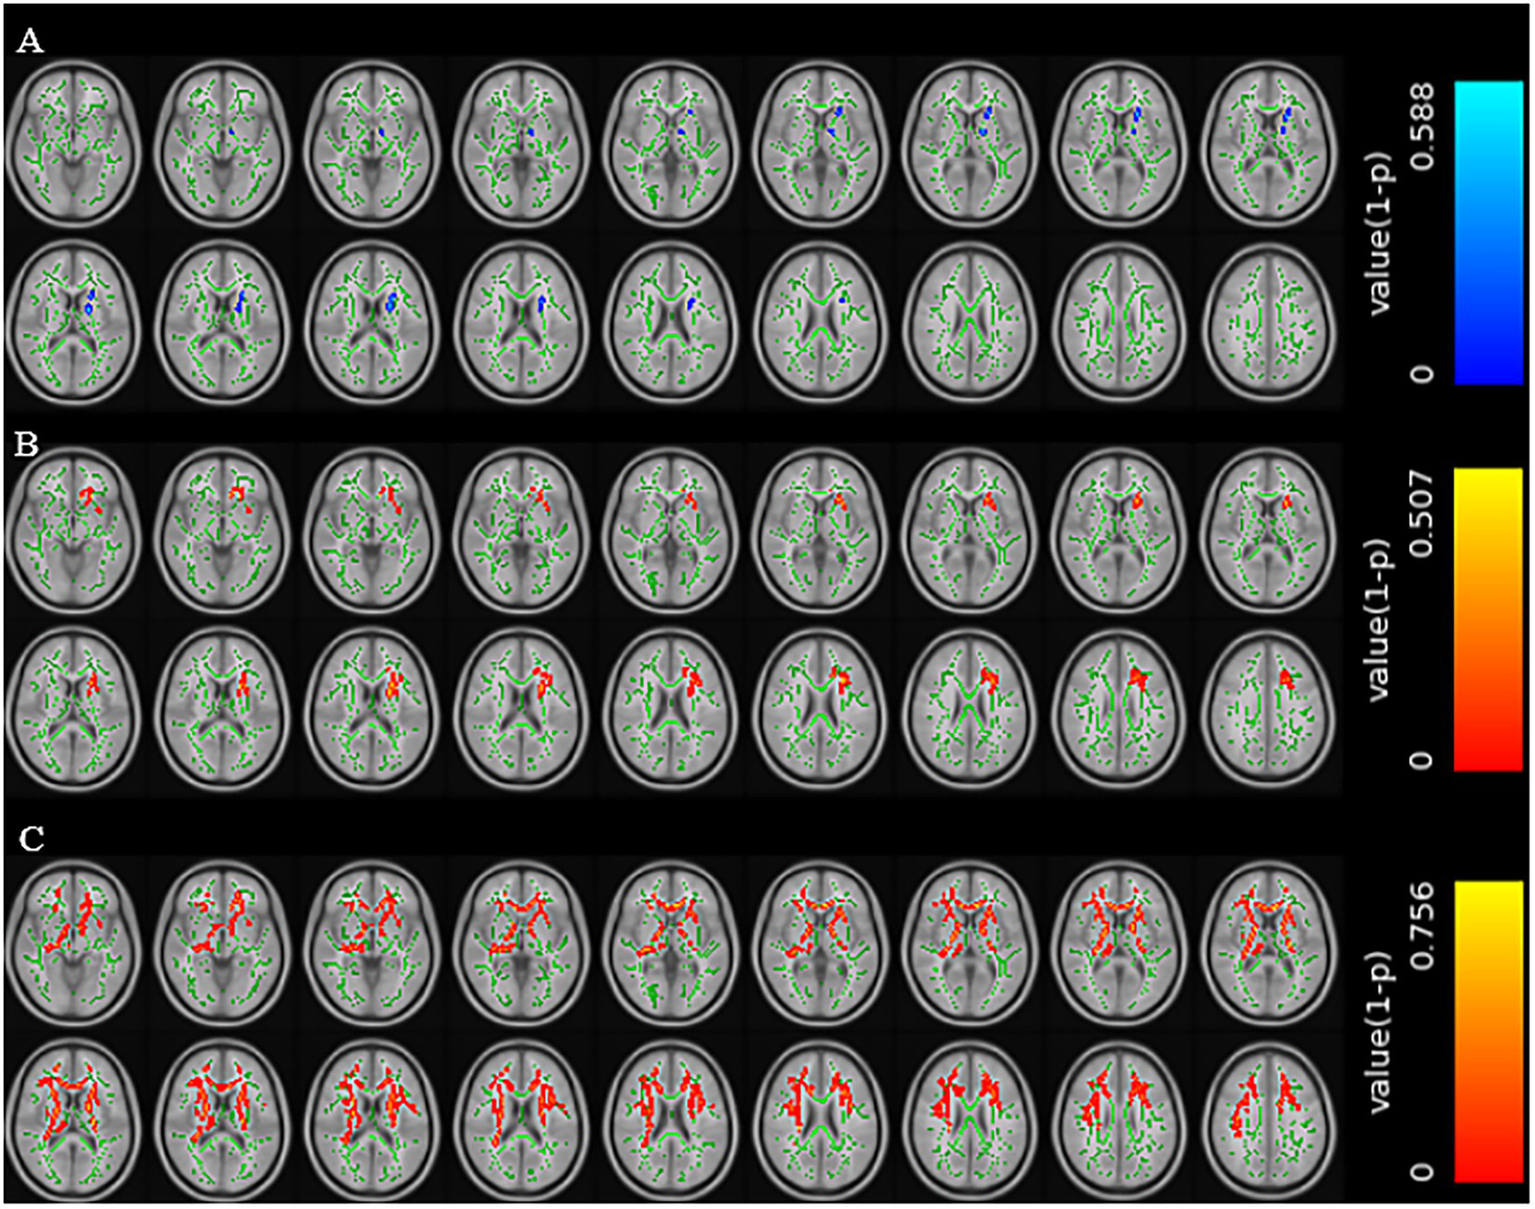

Variable selection based on univariate logistic regression and model performance

Compared with patients without cognitive impairment, patients with cognitive impairment showed decreased FA values in the left anterior limb of the internal capsule, left posterior limb of the internal capsule, left anterior radiation, and left superior radiation (TFCE corrected, p < 0.01); increased MD values in the genu of the corpus callosum, body of the corpus callosum, left anterior limb of the internal capsule, left anterior radiation, left superior radiation, left external capsule, and left superior fronto-occipital fasciculus (TFCE corrected, p < 0.01); and increased RD values in multiple regions including the genu and body of the corpus callosum, bilateral anterior and posterior limbs of the internal capsule, bilateral superior and anterior radiation, and several other tracts (TFCE corrected, p < 0.01) (Figure 2).

MRI scan images of a brain shown in three rows labeled A, B, and C. Each row contains multiple cross-sectional images with colored overlays. Row A includes blue, row B has red, and row C shows more intense red overlays. Each row uses a color scale on the right, indicating statistical significance, with blue to red denoting low to high values.

Figure 2. Brain regions with reduced FA values in the CSVD group with cognitive impairment (A). Brain regions with increased MD values in the CSVD group with cognitive impairment (B). Brain regions with increased RD values in the CSVD group with cognitive impairment (C) (TFCE correction, p < 0.01).